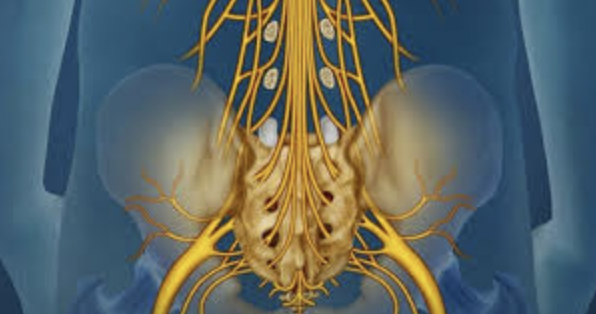

5. Bệnh lý thần kinh hoặc tuần hoàn

Người bị tiểu đường, rối loạn tuần hoàn có thể gặp tình trạng đau rát, tê buốt ở ngón chân, đặc biệt khi thời tiết lạnh.